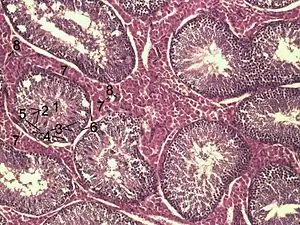

![]() Гистологический срез тестикулярной паренхимы кабана. 1 полость семенного канальца 2 – сперматиды, 3 — сперматициты, 4 — сперматогонии, 5 — клетки Сертоли, 6 — миофибробласты, 7 — клетки Лейдига, 8 — капилляры | |

Поперечное сечение семенного канальца крысы (x250)